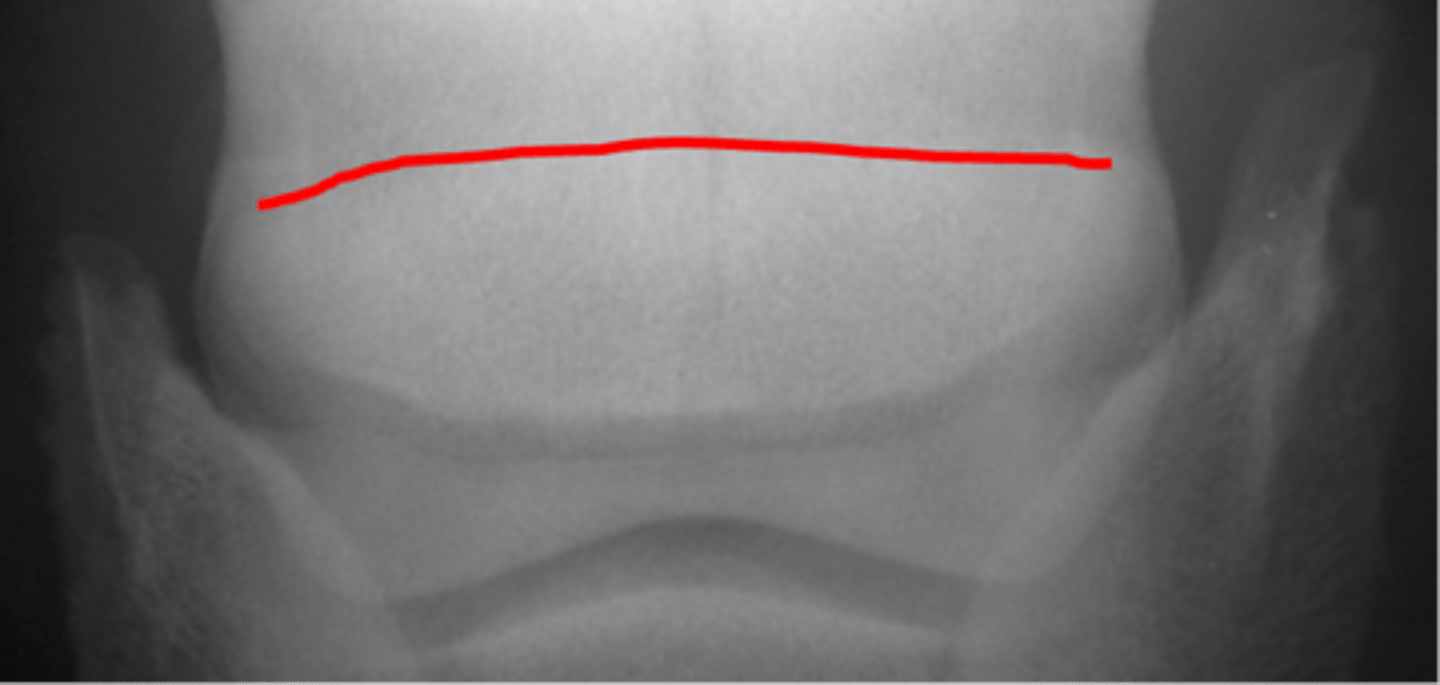

Navicular bone

Flexor cortex

Navicular bone

Proximal border of navicular bone

Distal border of navicular bone

Synovial invaginations

Flexor skyline

What view is this?

1. Flexor surface

2. Corticomedullary distinction

3. Number of synovial invaginations

What is the flexor skyline used to evaluate?

Navicular bone

Articular surface of navicular bone

Flexor surface of navicular bone

Sagittal ridge

Synovial invaginations